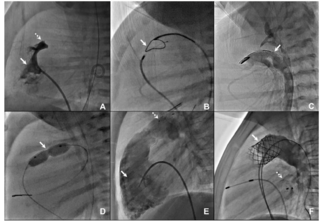

A woman in her 60s presented with symptomatic complete heart block and was advised permanent pacemaker implantation. During the procedure, left axillary vein access was attempted using fluoroscopic landmarks but was not successful. A venogram...